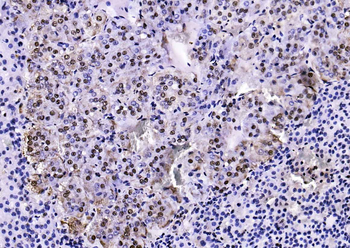

50 μl, 100 μl, 25 μl - CD14 Recombinant Rabbit Monoclonal Antibody [orb608064]Featured

IF, IHC-Fr, IHC-P, WB

Human

Rabbit

Recombinant

Unconjugated

100 μl, 50 μl, 25 μl - Rad51 Recombinant Rabbit Monoclonal Antibody [orb608069]Featured